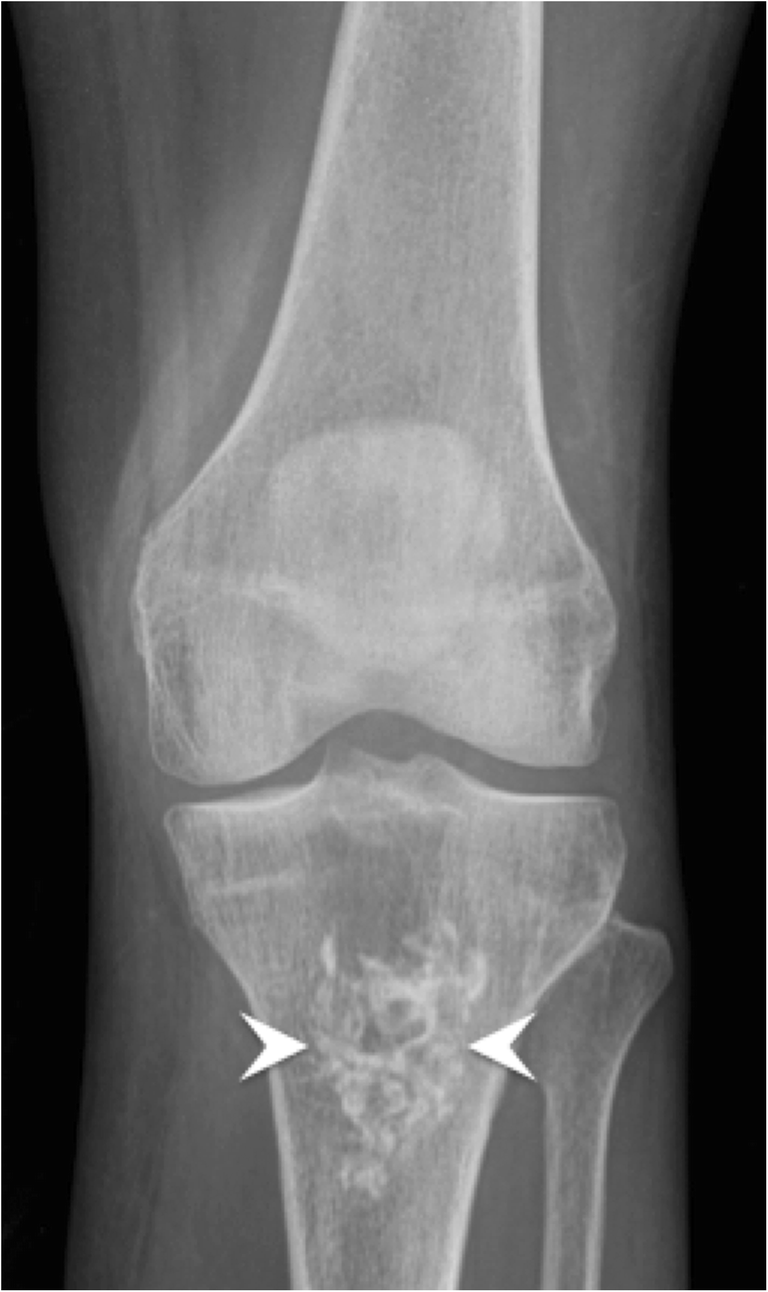

LearningRadiology Enchondroma Ring Bone Xray An arthritic, degenerative disease of the pastern and coffin joints, ringbone comes in two types. Horses of all breeds, ages, and functions can be at risk. But if we don’t get an answer with x rays, we can do mri, bone scans (aka nuclear scintigraphy), or ultrasound. The joint surfaces are usually very. “most of the time, diagnostics will. Ring Bone Xray.

From pubs.rsna.org

Diagnostic Imaging of Benign and Malignant Osseous Tumors of the Ring Bone Xray ringbone is a disease that does not discriminate; An arthritic, degenerative disease of the pastern and coffin joints, ringbone comes in two types. High ringbone affects the pastern, and low ringbone affects the coffin. Horses of all breeds, ages, and functions can be at risk. ringbone is a form of osteoarthritis in horses which affects the coffin joint. Ring Bone Xray.